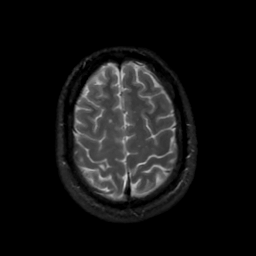

MR Study #16, June 23, 1991 -- Slice #41

[Home][Help][Clinical][Tour 1][Tour 2] Slice 41